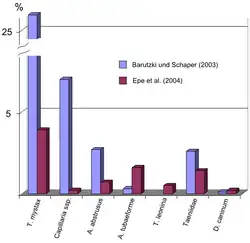

The frequency of infestation varies greatly depending on the worm species. In a German study of 3167 domestic cats, endoparasites were detected by flotation in 24% of the animals, with T. mystax showing the highest infestation rate at 26%.[17] Another study of 441 fecal samples detected T. mystax in only 3.9% of the samples, but again this roundworm was the most common parasite.[18] Infestation with T. mystax also dominates in Belgium,[19] the Netherlands,[20] the United Kingdom,[21] the United States,[22][23] Australia,[24] and Nigeria,[25] where infestation rates are as high as 60%. In Qatar, on the other hand, tapeworms (T. taeniaeformis: 76%, dipylidiidae: 43%) were mainly observed in stray cats, and T. mystax in only 0.4% of the animals.[26]